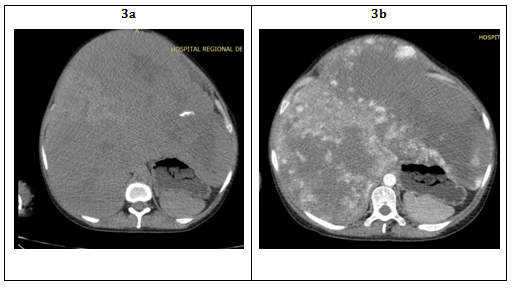

Physical examination is usually normal without significant findings, only rarely the hemangioma is presented as a large abdominal mass and an arterial murmur in the upper quadrant (Figure 1). Complications will depend on the location of the tumor and is generally present in cases of giant hemangiomas (HHG). It has been described circulatory shock and hemoperitoneum with spontaneous rupture, lower extremity edema by compression of the inferior vena cava in HHGs located in the caudate lobe. Compression of adjacent structures such as the stomach that can lead to gastric obstruction, bile ducts compression can lead to jaundice and hemobilia, colon compression can lead to volvulus or torsion, high expenditure heart failure due to massive arteriovenous shunt generally in children. Also can present hypothyroidism refractory to hormone therapy due to the presence of high levels of iodothyronine, deiodinase type 3 that favors the conversion of thyroxine and triiodothyronine to biologically inactive hormones and more rarely can present Kasabash Merritt syndrome (SKM).2,4,5

Figure 1 Front and profile’s patient photo with show large asymmetrical abdominal mass.

Photos from the department of Gastroenterology, Hospital Regional Docente de Enfermedades Neoplásicas